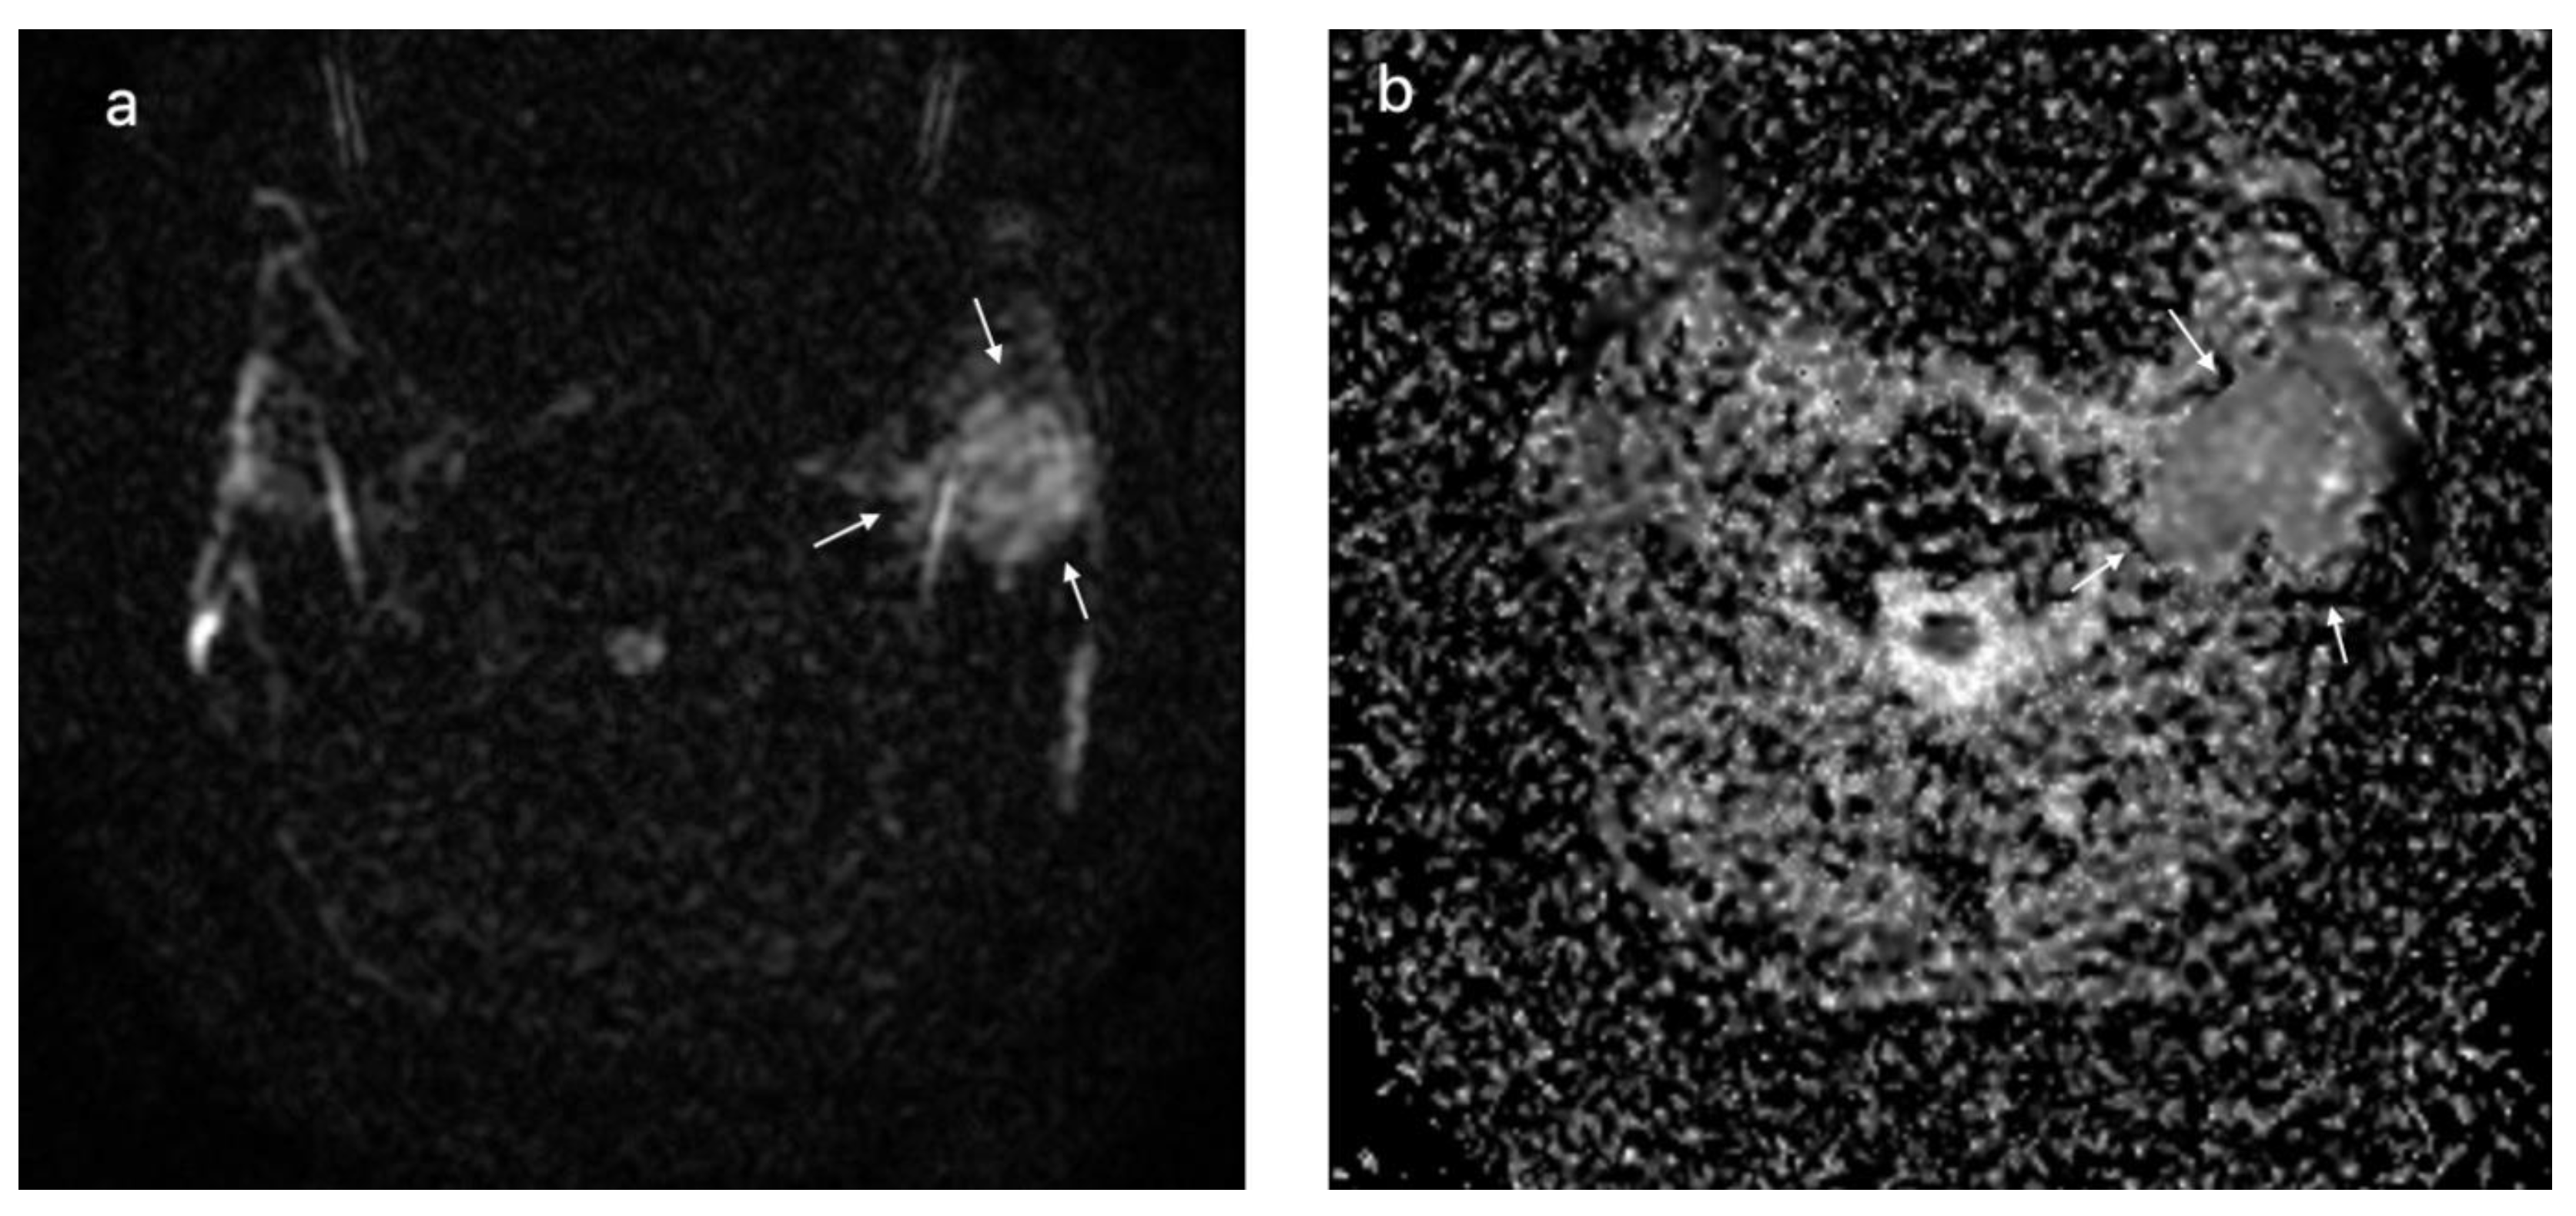

| DWI MRI, ADC × 10−3 mm2/s, median (IQR) | 1.03 (0.8–1.44) | 0.78 (0.68–0.99) | 0.024 |

| DWI MRI, ADC × 10−3 mm2/s, median (IQR) | 1.5 (1.25–2.1) | 0.86 (0.73–1) | <0.001 |